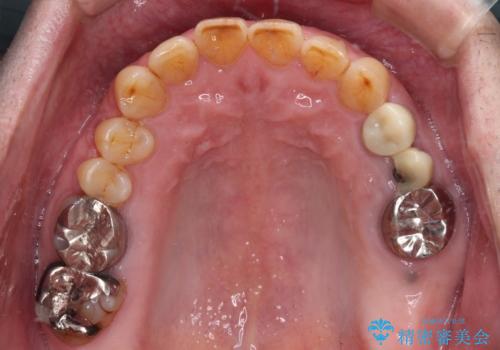

下顎大臼歯の抜歯決断までに時間がかかったため、治療期間はやや長くなりましたが、安定した咬み合わせとなり、痛みもなく安心して噛めるようになりました。

診察をしたところ、上下大臼歯の歯肉に排膿路認められたため、根管治療を行い、その後補綴治療を行うこととしました。

また、上顎の欠損部位にはインプラント治療を行うこととしました。